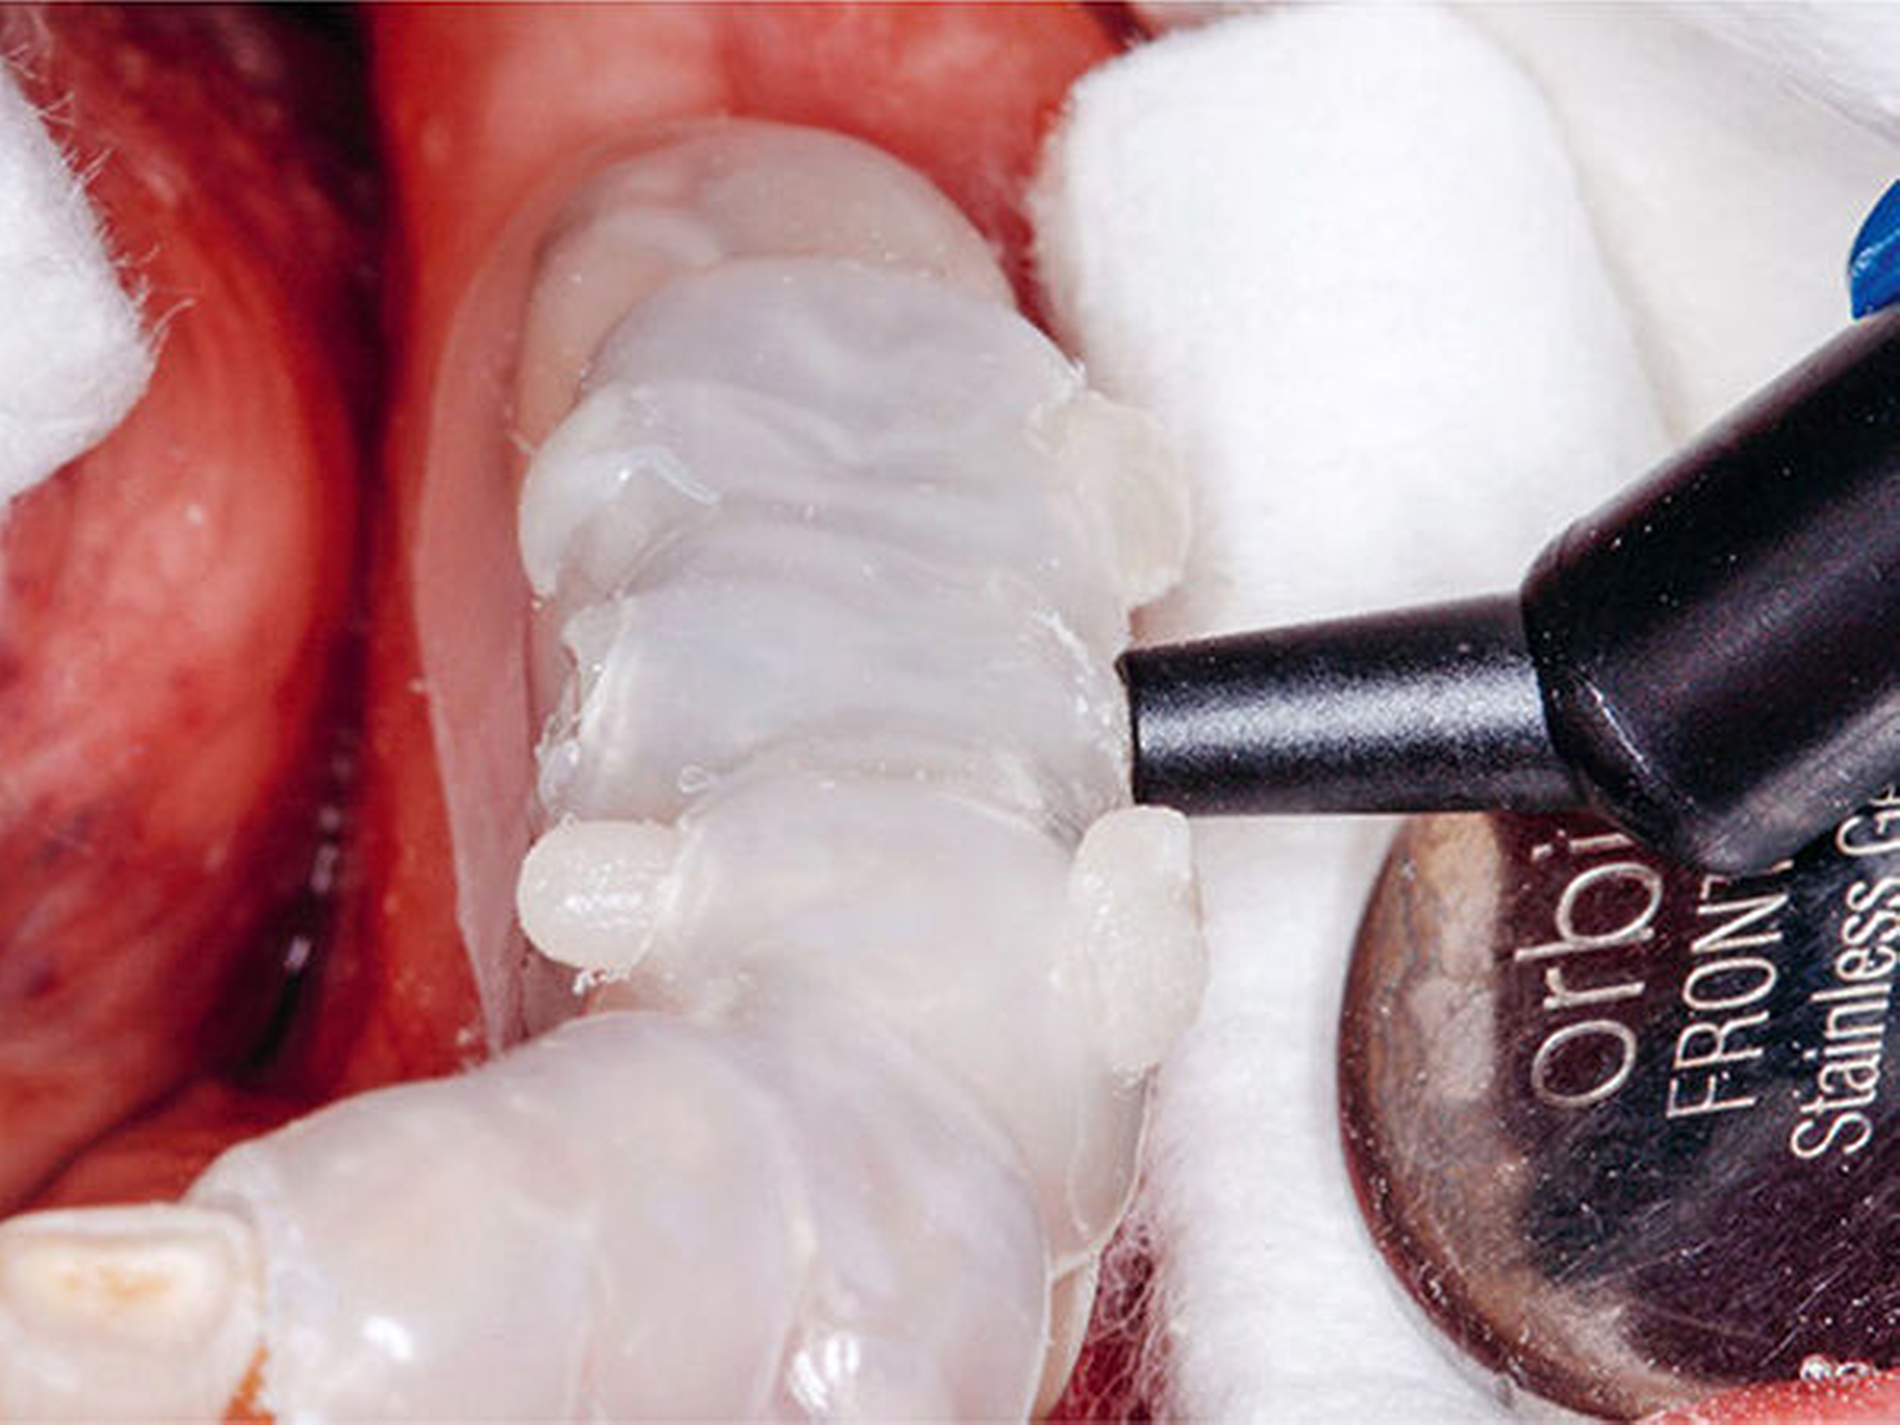

Ein abrasionsstabiles, seitenzahntaugliches, normalvisköses Hybridkomposit – in der Darreichungsform von Kompulen, um eine direkte intraorale Applikation unter Druck in die Hohlform der Schienen zu ermöglichen – wurde in ausreichender Kompulenzahl in einem wasserdichten Plastikbeutel im Wasserbad erwärmt, um die Viskosität temporär herabzusetzen. Die Kompulen mit dem erwärmten Komposit wurden aus dem Wasserbad entnommen, schnellstmöglich intraoral an die bukkalen Einspritzöffnungen der Übertragungsschienen „angeflanscht“ und deren Inhalt unter Druck in den Hohlraum eingespritzt, bis auf der oralen Schienenseite überschüssiges Kompositmaterial aus den Entlüftungsöffnungen austrat (Abb.23).

Während des Einspritzens des erwärmten Komposits in die Hohlform der Schienen müssen diese von der Assistenz an den mesialen bzw. distalen Abstützpunkten gut fixiert werden, damit sich die Schienen durch den Druck des einfließenden Materials nicht bewegen und somit Passungenauigkeiten entstehen. Es ist darauf zu achten, dass das komplette Hohlraumvolumen jeder einzelnen Schiene, welches entsprechend der jeweiligen Größe den Inhalt mehrerer Kompositkompulen aufnehmen kann, möglichst schnell aufgefüllt wird. Dies gelingt mit der Hilfe einer zweiten Assistenzperson, die schnell unmittelbar nacheinander mehrere Kompositapplikationspistolen mit erwärmten Kompulen anreicht, damit sich die Kompositmassen der einzelnen Kompulen im noch erwärmten Zustand im Schienenhohlraum blasenfrei miteinander verbinden. Dadurch entstehen im Bereich jedes Schienenhohlraums verblockte Kompositsegmente. Das erwärmte Komposit kühlt durch den Kontakt mit den mundwarmen Restaurationen bzw. Zähnen durch Konduktion sehr schnell ab und erreicht innerhalb von Sekunden wieder seine ursprüngliche hochvisköse Konsistenz (Abb.23).

Dieser Vorgang entspricht dem in der Industrie weitverbreiteten Spritzgussverfahren in der Kunststoffverarbeitung, in dem ein plastifizierter Werkstoff unter Druck in eine formgebende Urform (Hohlraum) eingespritzt wird und nach Abkühlung oder durch eine Vernetzungsreaktion wieder den festen Zustand einnimmt (Hornbogen et al. 2012). Durch die hohe Wärmekapazität der Restaurationen bzw. Zähne, die relativ geringe Menge erwärmten Kompositmaterials und die Möglichkeit der schnellen zusätzlichen Wärmeableitung in die Mundhöhle besteht bei Anwendung dieser Technik im Regelfall keine Gefahr einer thermischen Pulpaschädigung der betroffenen Zähne. Dieses Vorgehen sollte natürlich bei Zähnen mit pulpa-nahen Kavitätenanteilen modifiziert werden, indem diese Bereiche zuerst mit einer konventionell applizierten Kompositschicht abgedeckt werden. Nach der Aushärtung des ersten aufgebauten Kauflächenbereichs mit einer leistungsstarken Polymerisationslampe wurde die Übertragungsschiene mit einem Skalpell geschlitzt und abgenommen. Es resultierte eine perfekte Übertragung der anatomischen Strukturen des Wax-up in das intraorale Okklusalsegment aus Komposit (Abb.24).